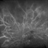

- Condition/keywords

- nonproliferative diabetic retinopathy, fluorescein angiogram (FA)

- Shelby Helton, Retina Specialist of Michigan

- Fundus camera

- 84-year-old male with Severe NPDR.